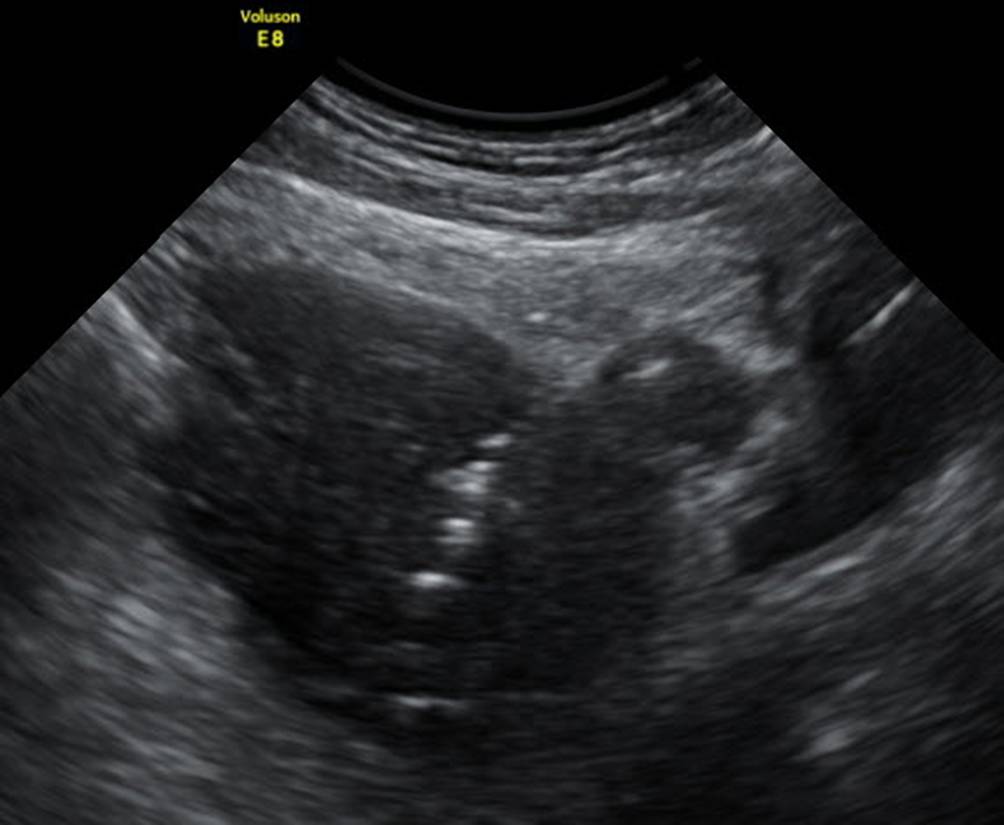

Abb. 14

Uterus mit Aszites bei OHSS, die Endometriumdicke wird mit 15 mm gemessen